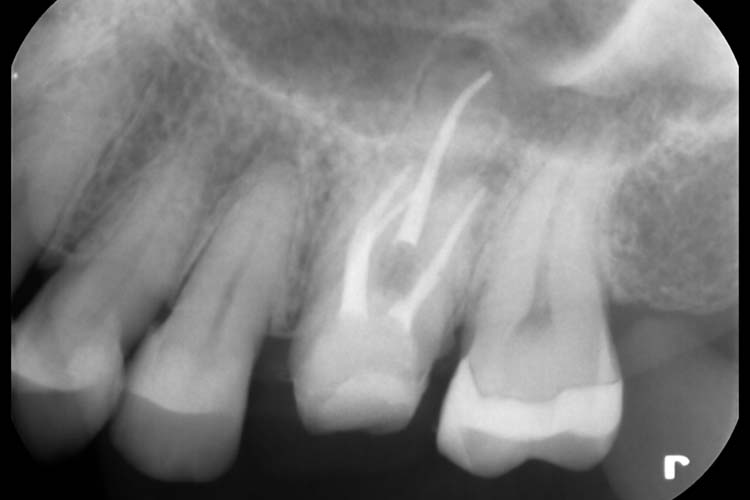

症例2

BEFORE

AFTER

| 主訴 | 左下の歯茎が腫れていて、何もしなくても歯が痛い。 |

|---|---|

| 治療期間 | 4回 約1ヶ月半 |

| 治療費 | 保険診療 |

| 治療内容 | 感染根管処置(根管治療) |

| 治療のリスク | 根管治療後、一時的に歯の根に痛みや違和感が生じることがあります。 |